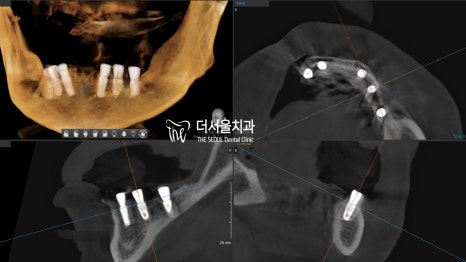

CT를 통해 확인해 보니 정확하게 심어져 있네요.

골융합이 잘 이루어질 수 있을까,

초기 고정력을 얻을 수 있을까

걱정이 들었지만 다행히 깔~끔하게 고정을 얻고 있었습니다.

어느 정도 회복될 기간을 부여한 뒤,

ISQ 측정을 통해 심어놨던 네비게이션 임플란트 가

문제없이 안정성을 얻고 있는지 확인을 했습니다.